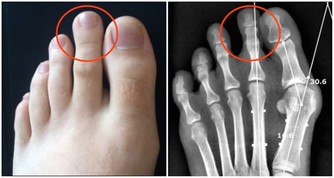

從秋分開始,天氣慢慢轉涼,晝夜溫差較大,氣候變化也無規律,是各種疾病的高發季節。同時,因為天氣乾燥,易出現咽乾、舌乾、少津、乾咳、少痰、皮膚乾裂等現象,也就是中醫學所說的“秋燥”。

需要注意的是,同樣是秋燥,也有溫燥、涼燥之分。一般而言,從秋分開始,人們的秋燥症狀多屬於涼燥。秋分前還有暑熱餘氣,多見溫燥;秋分後,秋風陣陣加上氣溫多變,開始出現涼燥,通常會有頭痛發熱、鼻塞流涕、唇燥咽乾、乾咳連連等症狀。